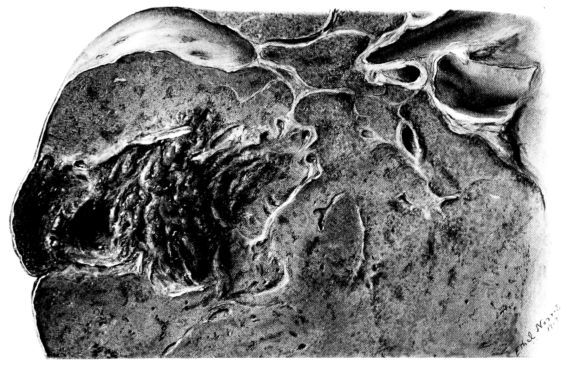

FIG. II. AUTOPSY NO. 98. DRAWING OF A SECTION THROUGH A TRACHEA SHOWING NECROTIZING HEMORRHAGIC INFLAMMATORY PROCESS OF THE MUCOSA.

The changes are less marked, perhaps, in the trachea than in its finer ramifications. The mucosa is constantly more or less destroyed and large areas, usually focal, are entirely devoid of their epithelial covering. This is replaced by a sparse exudate, composed largely of red blood cells, mucus, a small amount of fibrin, and nuclear fragments (Fig. II). It may dip into the submucosa for a short distance, but usually these indentures are associated with the ducts of the mucous glands into which the inflammatory reaction extends. A more striking feature than the exudate, however, is the edema and the congestion of the submucosa. The loose areolar tissue of the submucosa is spread widely apart, and throughout it distended blood vessels are very conspicuous. Occasionally such a vessel is broken and actual hemorrhage appears in the submucosa. Occasionally, too, the inflammation extends down the duct to the mucous gland itself, and here, also, aplastic inflammatory reaction is evident, inasmuch as the acini now stain intensely red with the cells undifferentiated from each other and specked here and there by broken remains of the dead nuclei (Fig. III). After the disease has continued for a short period, even at the end of five or six days, some regeneration of the epithelial lining may be seen (3) (Fig. IV). But despite this, the acute picture persists, and there goes on, side by side, an attempted repair characterized by epithelial regeneration and the same evidence of acute change. Since the lesion is essentially a superficial one, scars or contractures of any extent are not encountered in the trachea, even in examples of the disease that have ended fatally only after many weeks.[4]